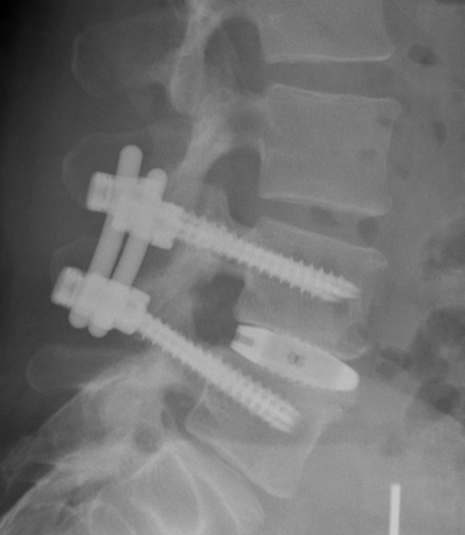

Osteochondrose

Der Begriff Osteochondrose beinhaltet den Verschleiß eines oder mehrerer Bewegungssegmente der Wirbelsäule. Häufigste Lokalisation ist der Zwischenwirbelraum der unteren Lendenwirbelsäule. Dabei kann es durch den Verschleiß der Bandscheibe zur lokalen Rücken/Nacken-Beschwerden kommen oder durch daraus resultierende Instabilität eine Spinal- oder Nerveneinengung mit ausstrahlenden Beschwerden verursachen. Im fortgeschrittenen Stadium kann dies auch zu ausgeprägten Wirbelsäulenverkrümmungen führen, die dann möglicherweise einen "Ganzwirbelsäulenschmerz" verursachen. Die Therapie der Wahl bei Osteochondrose an der Lendenwirbelsäule ist nach Ausschöpfung der konservativen Therapiemaßnahmen die Spondylodese oder Versteifung. Dabei werden nur die betroffenen Bereiche mit einem Schraubenstabsystem überbrückt und die verschlissenen Bandscheiben durch einen Platzhalter ersetzt.

Beispiel Osteochondrose